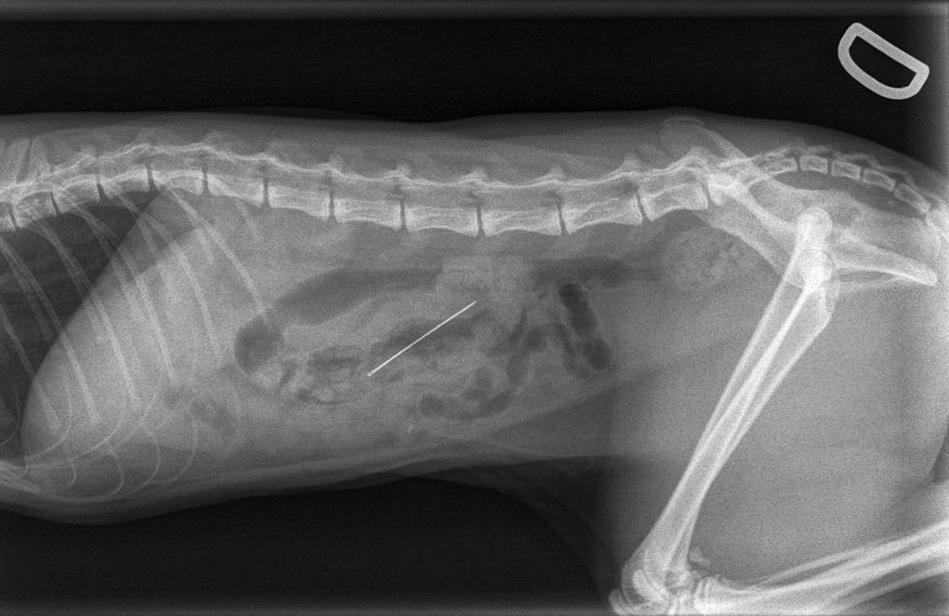

Voici l’histoire de Zelda, une adorable chatte Rex Cornish de 1 an qui a été présentée en urgence à notre clinique. Tandis qu’elle jouait avec un fil à la maison, sa propriétaire l’a vu avaler ce fil… ainsi que l’aiguille à coudre qui se trouvait au bout! Elle s’est donc déplacée rapidement afin de procéder à son examen physique complet. Puisque l’examen approfondi de sa gueule ne démontra aucun fil ni aiguille, nous avons procéder à des radiographies de son abdomen. Comme une aiguille est assez dense pour être visible à la radiographie, il a été facile de constater que l’aiguille était située dans son système digestif.

Consciente des dommages importants que cette aiguille pouvait causer si elle perforait le système digestif de Zelda, sa propriétaire nous a donné l’autorisation pour procéder à la chirurgie. Une analyse sanguine complète a été effectuée et un soluté intraveineux a été mis en place avant la chirurgie afin d’assurer une sécurité anesthésique adéquate. Zelda a été anesthésié, son abdomen a été rasé et désinfecté avant qu’elle soit transférée en salle de chirurgie. Son abdomen a été ouvert et un examen minutieux de son système digestif a été effectué, permettant de localiser l’aiguille et de s’assurer qu’elle n’ait causé aucun dommage interne. L’aiguille et le fil ont été retirés, l’intestin fut refermé à l’aide de points de sutures et un lavage stérile de l’abdomen a été effectué avant la fermeture finale.